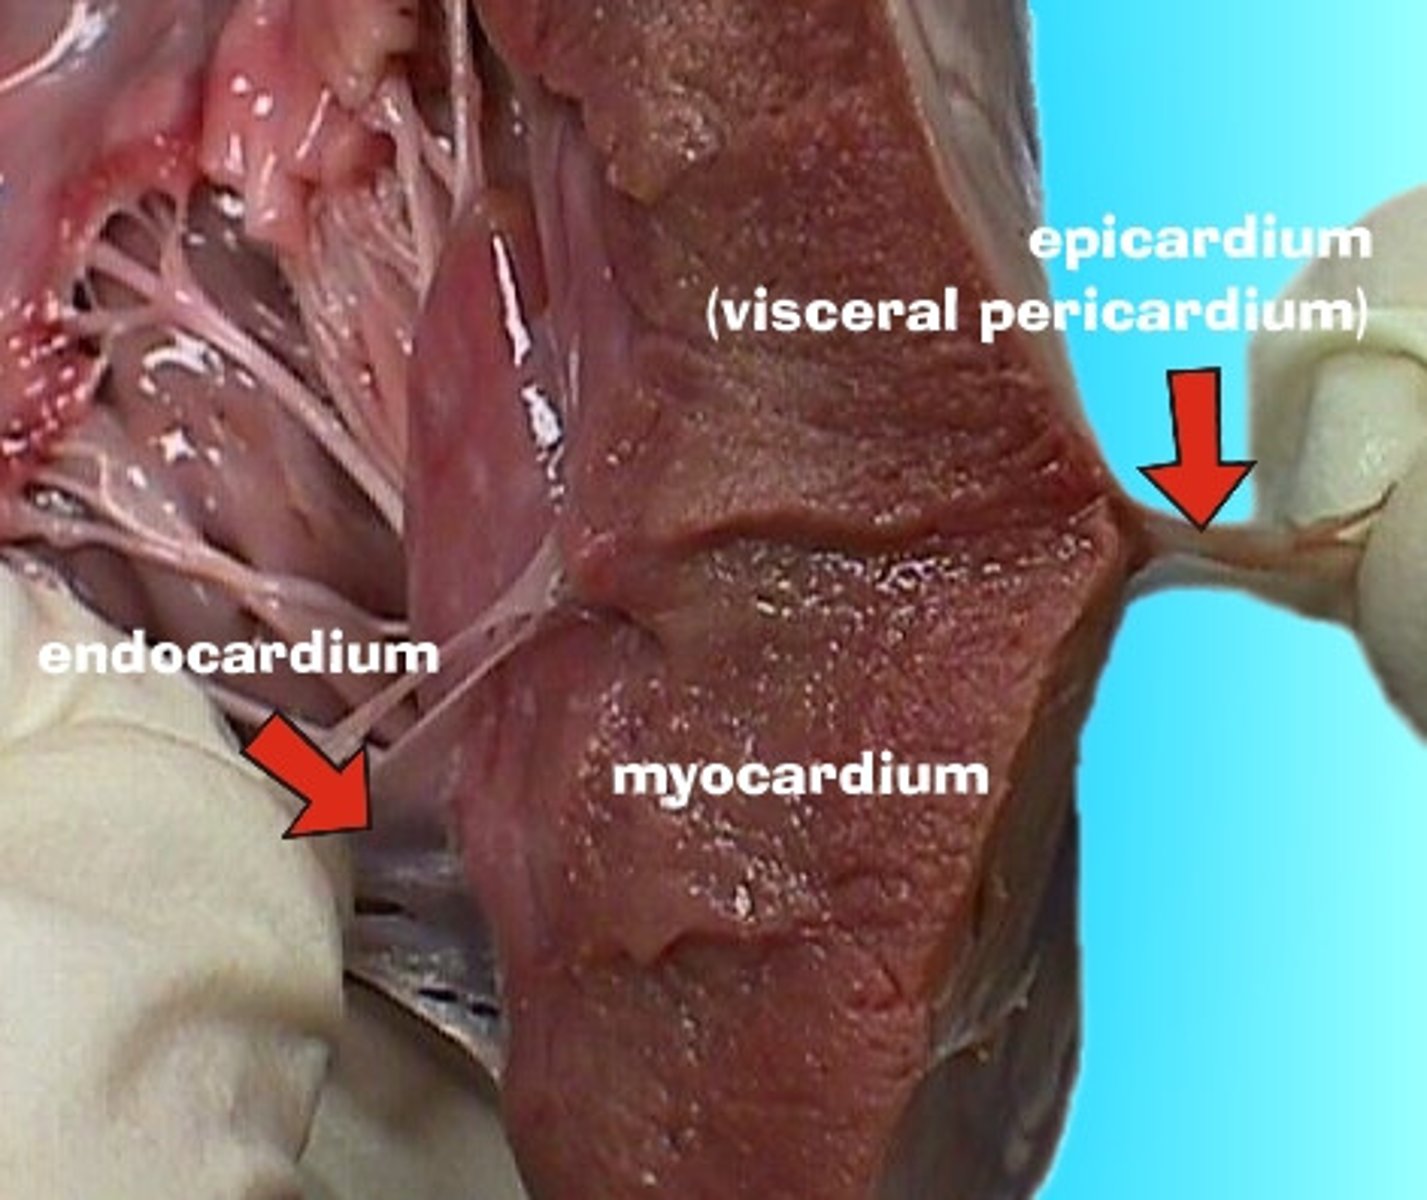

osierdzie

pericardium

Jakie rodzaje osierdzia wyróżniamy?

surowicze i włókniste

osierdzie surowicze

serous pericardium

Z jakich części składa się osierdzie surowicze?

z blaszki trzewnej i ściennej

blaszka trzewna osierdzia surowiczego

visceral layer of serous pericardium

blaszka trzewna osierdzia surowiczego inaczej

nasierdzie

nasierdzie

epicardium

blaszka ścienna osierdzia surowiczego

parietal layer of serous pericardium

Gdzie znajduje się jama osierdzia?

między blaszką ścienną i trzewną osierdzia surowiczego

jama osierdzia

pericardial cavity

Jak jest położone nasierdzie?

ściśle zrośnięte z powierzchnią zewnętrzną serca

Jak odróżnić blaszkę ścienną osierdzia surowiczego i osierdzie włókniste?

Nie da się - są ze sobą zrośnięte

Co znajduje się w jamie osierdzia?

płyn surowiczy umożliwiający ślizganie się blaszek osierdzia